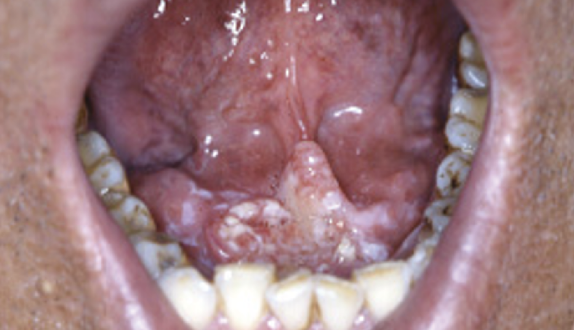

2. 구강암 증세 증상

구강암의 증상으로는 3주 이상 지속되는 궤양, 흰색 혹은 붉은색 병변, 구강 통증, 구강 내 혹은 목에 만져지는 종물, 쉽게 아물지 않는 구강 내 상처 등이 있습니다. 위와 같은 증상이 있다면 이비인후과 진료를 받는 것이 좋습니다.